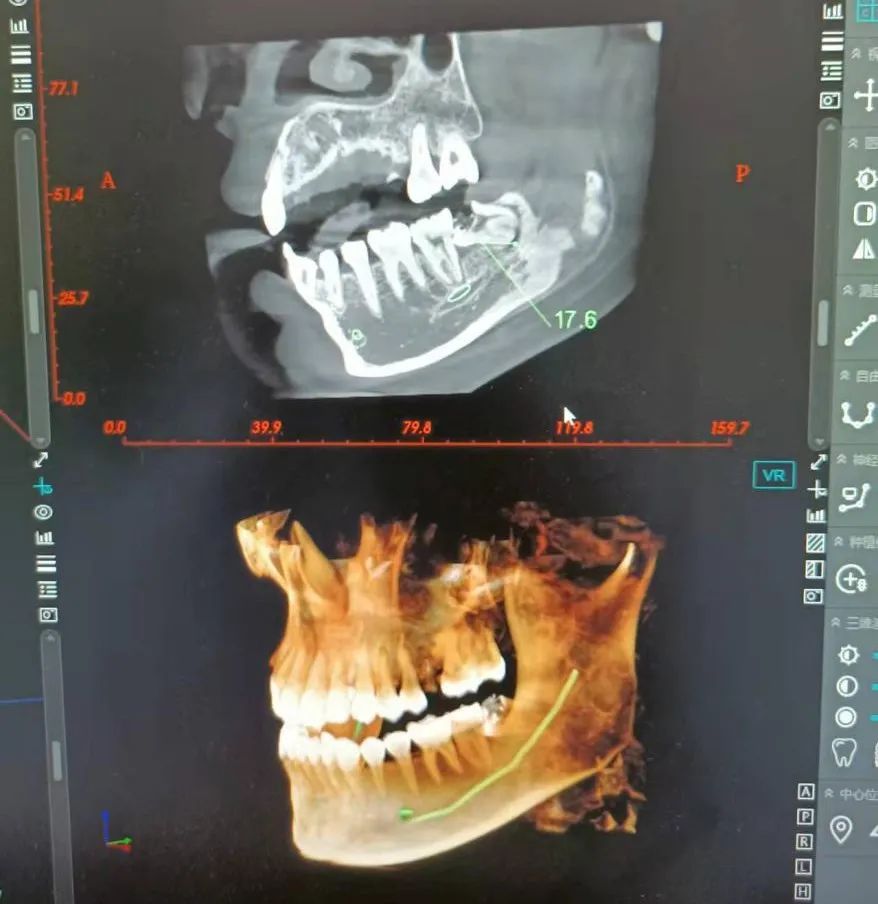

拔除此埋伏智齒手術(shù)難度較大

在衛(wèi)生部下發(fā)的《手術(shù)分級目錄》中"復雜阻生齒拔除術(shù)"屬于二級手術(shù),對開展手術(shù)的單位和醫(yī)生資質(zhì)都有嚴格的要求。復雜阻生齒臨近頜面部大的神經(jīng)、血管、上頜竇等重要解剖位置,實施復雜阻生齒手術(shù)定不可以輕心

科室配備國際先進牙科綜合治療臺、牙科x光機、口腔CT,超聲根管治療儀、種植牙系統(tǒng)、超聲潔牙機、牙周治療儀、微創(chuàng)拔牙系統(tǒng)等先進設備。